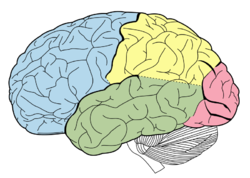

Temporallappen er afgrænset opad til mod lateral fissuren (fissura Sylvii), posteriort mod occipitallappen, postero superiort mod parietallappen, inferiort mod gulvet af fossa crani media, og medialt mod de præpontine cisterne og mod hjernestammen posteriort (Fig. 1). Den mesiale del af temporallappen er beskrevet mere i detaljer i siden om Hippocampus. Husk at gyri og sulci er "koncepter", de er ikke altid kontinuerlige, en gyrus kan således krydses af en sulci og stadig være den samme på den anden side af den pågældende sulci, eller splittes i to parallelle som tilsammen udgør en navngiven sulci. I figurene til høje er angivet såvel de normale gyrus navne, som de mere enkle T1-T5, T6 udgøres af hippocampus.

Lateralsiden af temporallappen udgøres af tre gyri adskilt af to sulci (Fig. 2). Gyrus superior (T1) og gyrus medius (T2) adskilles af sulcus superior, mens gyrus medius og gyrus inferior (T3) adskilles af sulcus inferior.